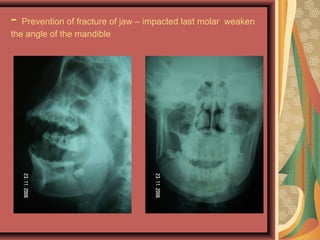

- Prevention of fracture of jaw

- Prevention of fracture of jaw – impacted last molar weaken

the angle of the mandible

- Prevention offracture of jaw – impacted last molar weaken the angle of the mandible

• 15.